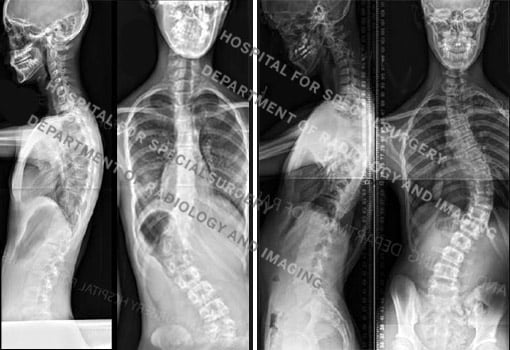

Figure 2a and 2b. Posteroanterior (back-to-front) X-rays of idiopathic scoliosis. At left are images of a 14-year-old girl with a left thoracolumbar curve measuring 47° and a right lumbar curve measuring 20°. At right, are images of a 15-year-old boy with a long thoracic curve measuring 60°.